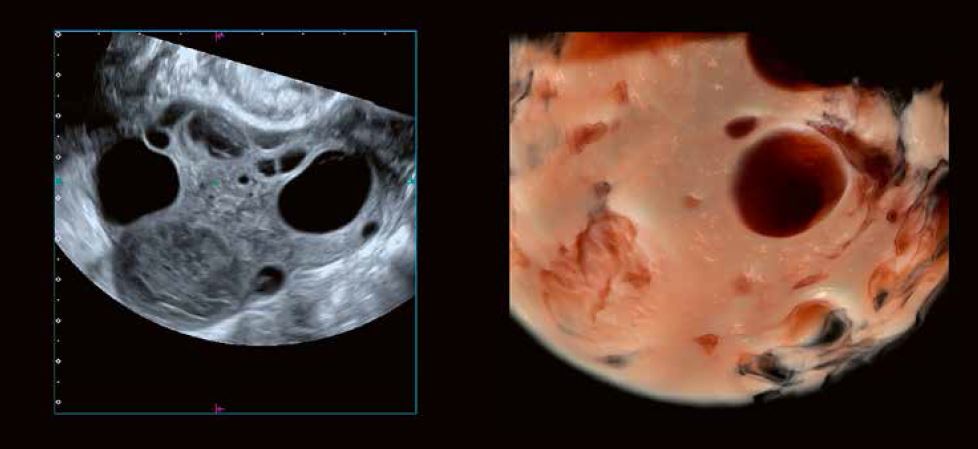

Рис. 1: Детальне зображення морфології яєчників  за допомогою 3D-реконструкції в сірій шкалі та візуалізації Shadow Glass відповідно. Розширена 3D-візуалізація візуалізує стійку, заповнену згустками лютеїнову кісту,  незрілі фолікули перед овуляцією, антральні фолікули,  а також атретичні фолікули та залишки фолікула, що пройшов овуляцію.

Протягом усього циклу між початком менструації та менопаузою кора яєчників підтримує фолікули на різних стадіях розвитку. Ті, що видно на ультразвуковому дослідженні, варіюються від багатьох антральних фолікулів до ряду незрілих фолікулів і, як правило, одного домінантного передовуляційного (граафського) фолікула (рис. 1 + 3).

Рис. 3 D: 2D- та 3D-зображення (Luminance) показують фолікули жінок у віці від 45 до 50 років. На відтвореному зображенні чітко видно контури фолікулів, що складаються з гранульозних та текальних клітинних шарів.

Кора містить початкові фолікули і підтримує їх перехід до преантральної стадії розвитку в рамках росту і дозрівання фолікулів. Фолікул на цій стадії складається з щільної або первинної ооцити, оточеної гранульозними клітинами, інкапсульованими комірцем клітин, що називаються текальними клітинами. Збільшення товщини гранульозних і текальних клітин відбувається з утворенням центрального скупчення рідини. Ці зміни призводять до утворення антрального фолікула.

«Кістозний» вигляд дозволяє візуалізувати антральні фолікули розміром від 2 до 3 мм. Розмір антральних фолікулів коливається від 2 до 8 мм. Підрахунок антральних фолікулів, що проводиться перед процедурами ЕКЗ або для оцінки фолікулярного запасу яєчників у пацієнток в періоді менопаузи, точно вимірюється за допомогою 3D УЗД вагінальним датчиком проводиться приблизно на 3–5 день циклу після початку менструації.

Ультразвукове дослідження та моніторинг росту фолікулів під час природного або пов'язаного з допоміжними репродуктивними технологіями циклу вже давно стали загальноприйнятою практикою. Прогрес у технології УЗД значно підвищив можливості оцінки дозрівання фолікулів та прогнозування початку овуляції (рис. 5). Сканування у високій роздільній здатності в сірій шкалі демонструє потовщення стінки фолікула внаслідок розвитку гранульозних та текальних клітин. Внутрішнє відшарування гранульозних клітин можна виявити в овуляційному фолікулі. 3D-візуалізація Fly Thru часто дозволяє розпізнати кумулюсну масу безпосередньо перед овуляцією (рис. 6). Розмір фолікула на початку овуляції може варіюватися від 1,8 до 3,0 см. Примітка: розмір фолікула сам по собі не завжди є показником його дозрівання.